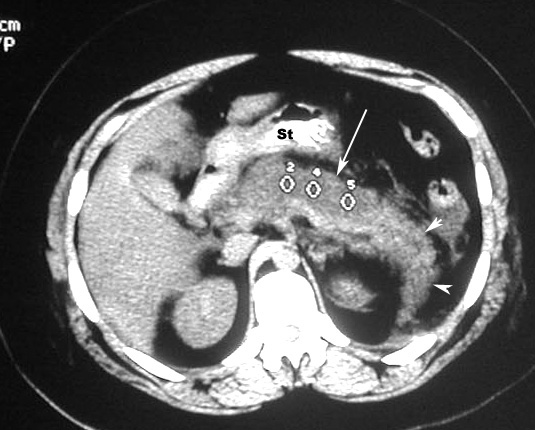

Acute Pancreatitis / Pancreatic necrosis

• Arrow: No enhancement of pancreas with IV contrast

• Arrowheads: Normal enhancement in the tail of Pancreas.

St: Stomach